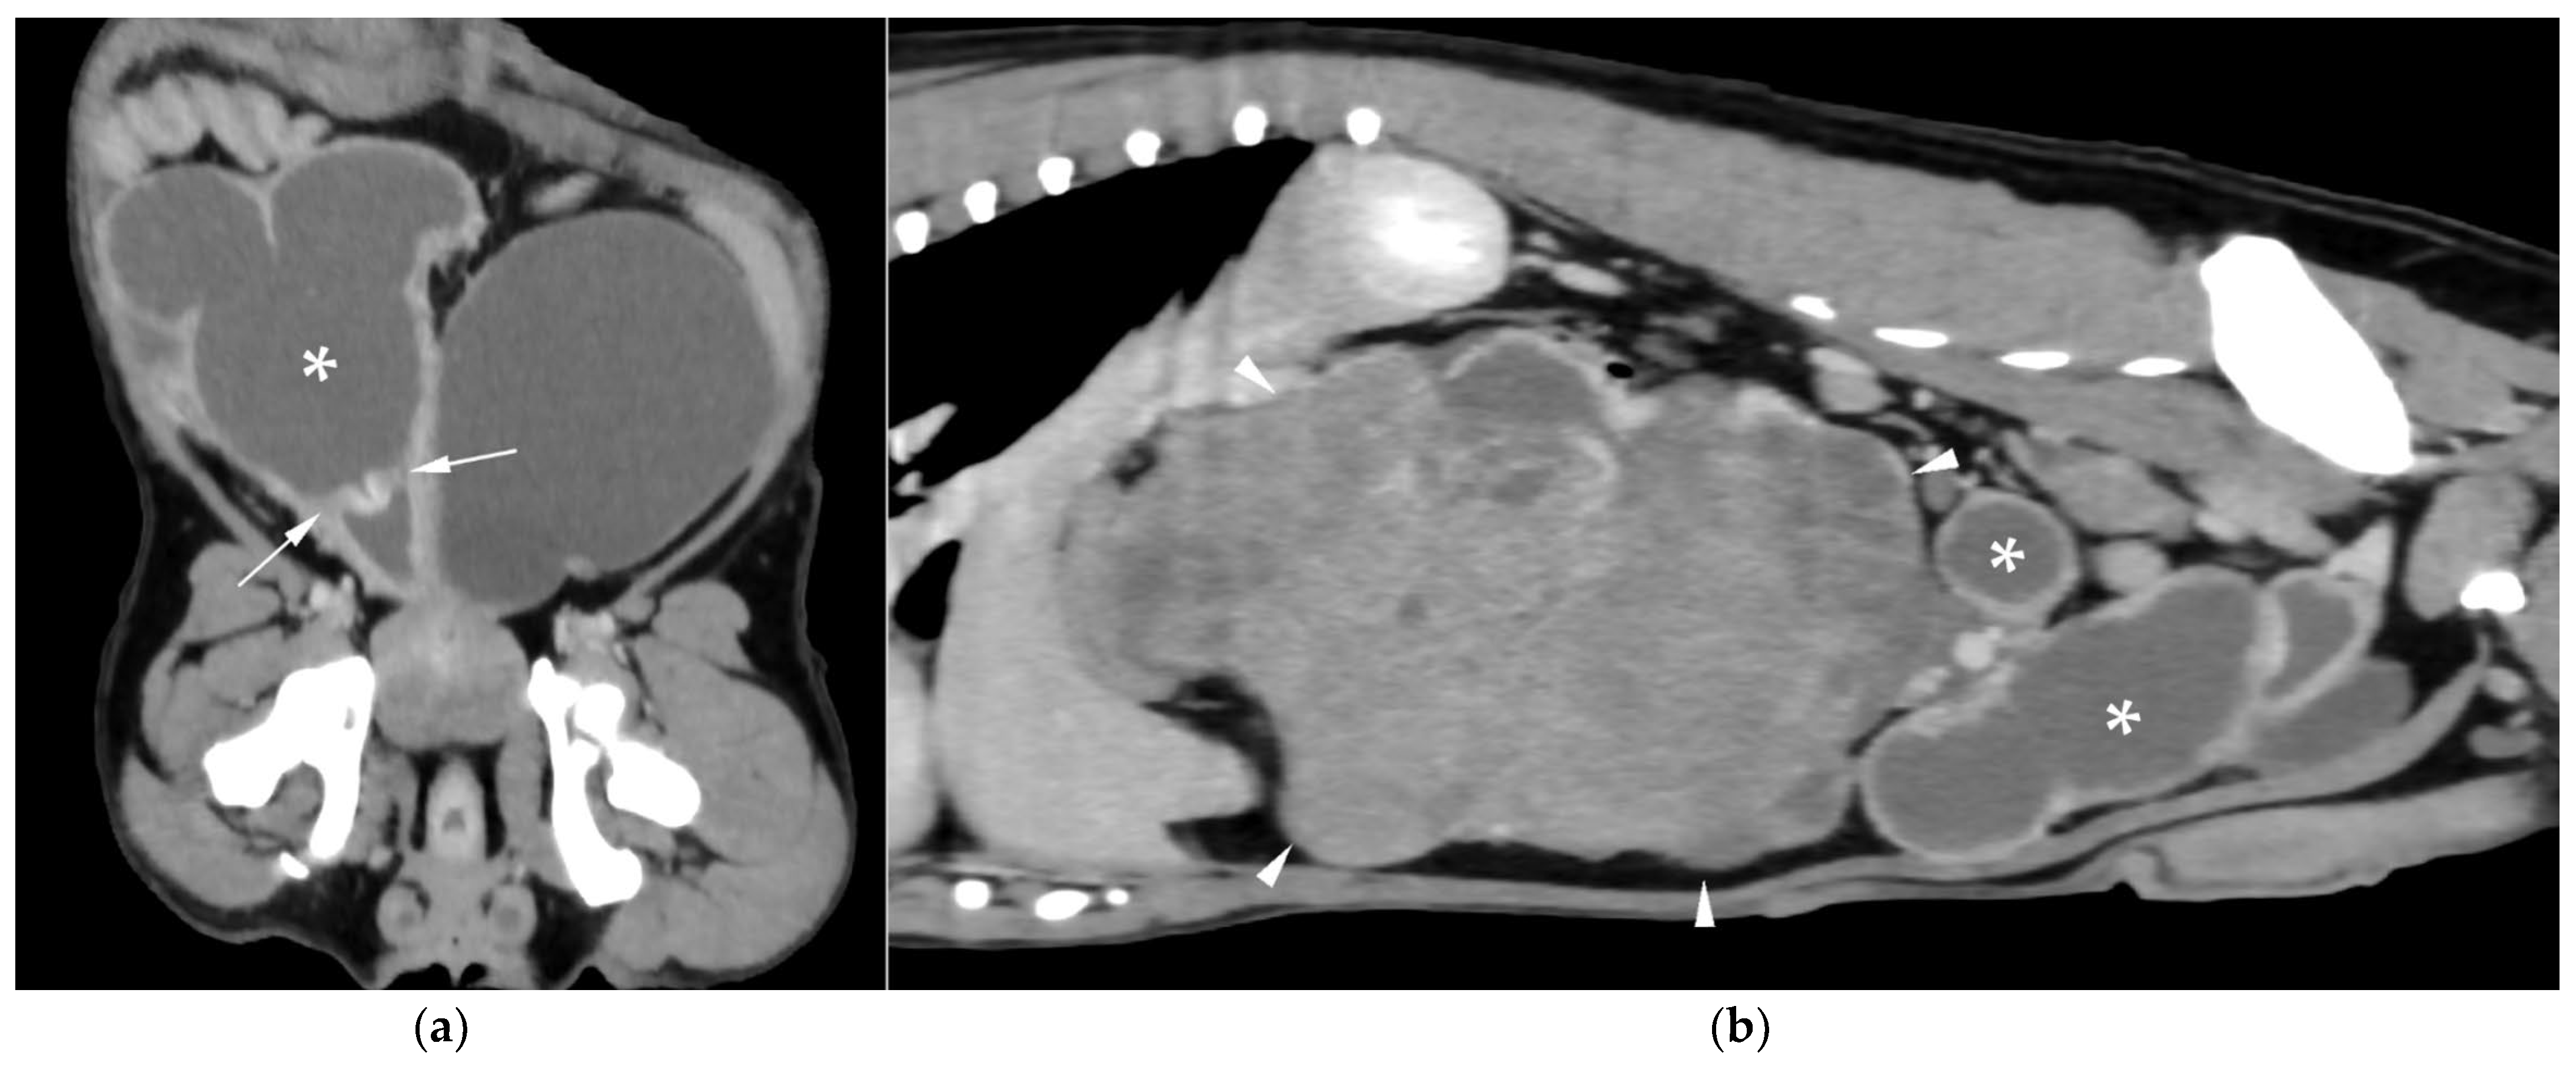

CT revealed a large cavitary structure arising from the craniodorsal aspect of the prostate and extending cranially through the mid-abdomen in each dog (Figure 4a, Figure 5a and Figure 6a). In cases 1 and 2, the structure consisted of a large central cavity, with bilateral horns, coursing caudally through the inguinal rings to each scrotal testis (Figure 4b and Figure 5b). The horns were fluid distended, except for the right horn in case 2, in which no lumen could be identified. In case 3, a Y-shaped bicornuate structure was identified (Figure 6a); the right horn terminated in a cranial peritoneal mass, while the left one ended in the mid-caudal abdomen.

All lesions had thin walls with moderate contrast enhancement, slightly irregularly marginated in cases 2 (Figure 5c) and 3, and smooth in case 1. In cases 1 and 3, moderate dilation involved the entire organ, with a focal mural narrowing resembling a cervix observed at the caudal aspect of the structure (Figure 4a and Figure 6a). In case 2, only minimal dilation of the most caudal portion of the UM was noted (Figure 5a). The luminal content was mildly hyperattenuating (10–20 Hounsfield units) in all cases. It was homogeneous except in the cranial portion of the UM of case 2, where attenuation was slightly higher in the gravity-dependent ventral aspect (20 Hounsfield units) compared with its dorsal aspect (11 Hounsfield units). In case 1, small dorsal bubbles of gas were also noted, likely due to prior drainage at the referring center.

In case 1, both testes were heterogeneous with irregular, ill-defined multifocal lesions after contrast; in case 2, a nodule was present in the left testis. In case 3, in continuation with the cranial end of the right uterine horn and intimately associated with engorged right gonadal vessels, a large, irregular, heterogeneous mass with moderate contrast enhancement was identified, causing a regional mass effect (Figure 6b). No structures compatible with a left gonad were detected in case 3, consistent with the previous unilateral orchiectomy.

Additional findings in all cases included: an enlarged, heterogeneous prostate with small hypoattenuating foci after contrast administration; free peritoneal fluid (moderate in case 2, mild in cases 1 and 3); and iliosacral lymphadenomegaly (moderate in cases 2 and 3, mild in case 1). Enlarged mammary glands and nipples were also noted in case 3.

Figure 4. Computed tomography (CT) of case 1: (a) Slightly oblique longitudinal view showing the UM, extending from the prostate gland (black asterisk), passing dorsally to the urinary bladder, at which level a cervix-like mural narrowing (arrowheads) is identified, with a more distended portion of the UM (white asterisk) cranial to it; (b) Slightly oblique dorsal view showing the distended UM (asterisk) cranial to the contrast-filled urinary bladder, with the uterine horns coursing caudally on both sides and running through the inguinal rings (arrows).

Figure 5. CT of case 2: (a) Slightly oblique longitudinal view showing the UM, extending from the prostate gland (black asterisk), not distended at this level (white arrowheads), through the mid-caudal abdomen, where a more distended portion of the UM (white asterisk) is identified. Ventral to it, there is a scant volume of peritoneal free fluid; (b) Dorsal view showing the UM (asterisk) on the left, with caudal extension of the left uterine horn through the inguinal ring into the scrotum (arrows), and the urinary bladder positioned on the right; (c) Transverse view depicting the urinary bladder on the right and three transverse sections of the UM (asterisk) on its left, surrounded by free peritoneal fluid. The two UM sections closest to the prostate show mild distention and irregular wall thickening (arrowheads).

Figure 6. CT of case 3 (a) Dorsal oblique view showing the UM (asterisk) on the right, with a cervix-like mural narrowing (arrows) and cranially extending paired uterine horns. The urinary bladder is positioned to the left, and the prostate lies caudal to them; (b) Parasagittal view demonstrating a large right-sided cranial peritoneal mass (arrowheads) with multiple sections of the UM (asterisks) caudal to the mass.